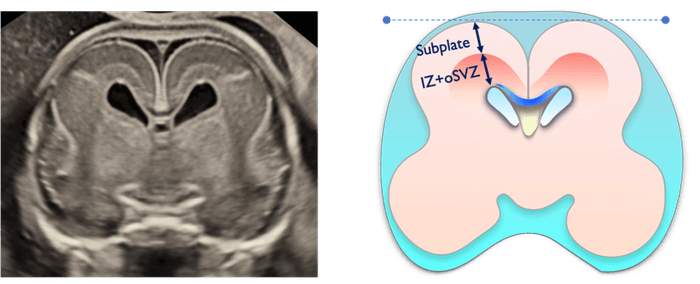

夫 律子院長が発表した研究は、胎児の脳における「サブプレート」と呼ばれる脳層に着目したものです。サブプレートは胎児期の一定の時期にしか観察されることがない特殊な脳層で、ヒトの大脳皮質形成初期においてニューロンの移動や神経回路の形成に重要な役割を果たし、神経発達の鍵を握る構造として注目されています。このサブプレートに着目して実際の胎児での観察実績をもつのは現在のところ世界でもクリフム出生前診断クリニックだけです。※当院調べ

方法:高精度3D経膣脳神経超音波による脳の詳細計測

結果:先天異常を持つ胎児群を複数のグループに分類し、サブプレートの発達パターンを比較分析した結果、グループ間で明確な発達の違いを確認。